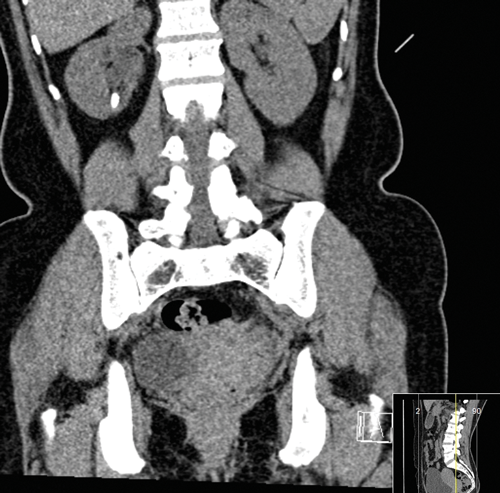

Figure 1a and b: CT images revealing the calyceal diverticular stone.

The mainstay of imaging is computed tomography kidneys, ureter and bladder (CTKUB) with pre and post contrast images (Figure 1). Pre-contrast imaging will enable detection of calculi and gross anatomical variations. Using contrast, an early phase calyceal diverticulum will appear as rounded a low attenuation area next to the calyces. The delayed contrast (excretory) phase will show filing of this area with minimal overlying cortex [17]. Differential diagnoses such as hydrocalyx, simple cysts, parapelvic cysts, tubercular cavity, papillary necrosis and renal tumours may be detected. The CT is vital for surgical planning as three-dimensional reconstruction can be undertaken to help plan the puncture for the percutaneous approach.